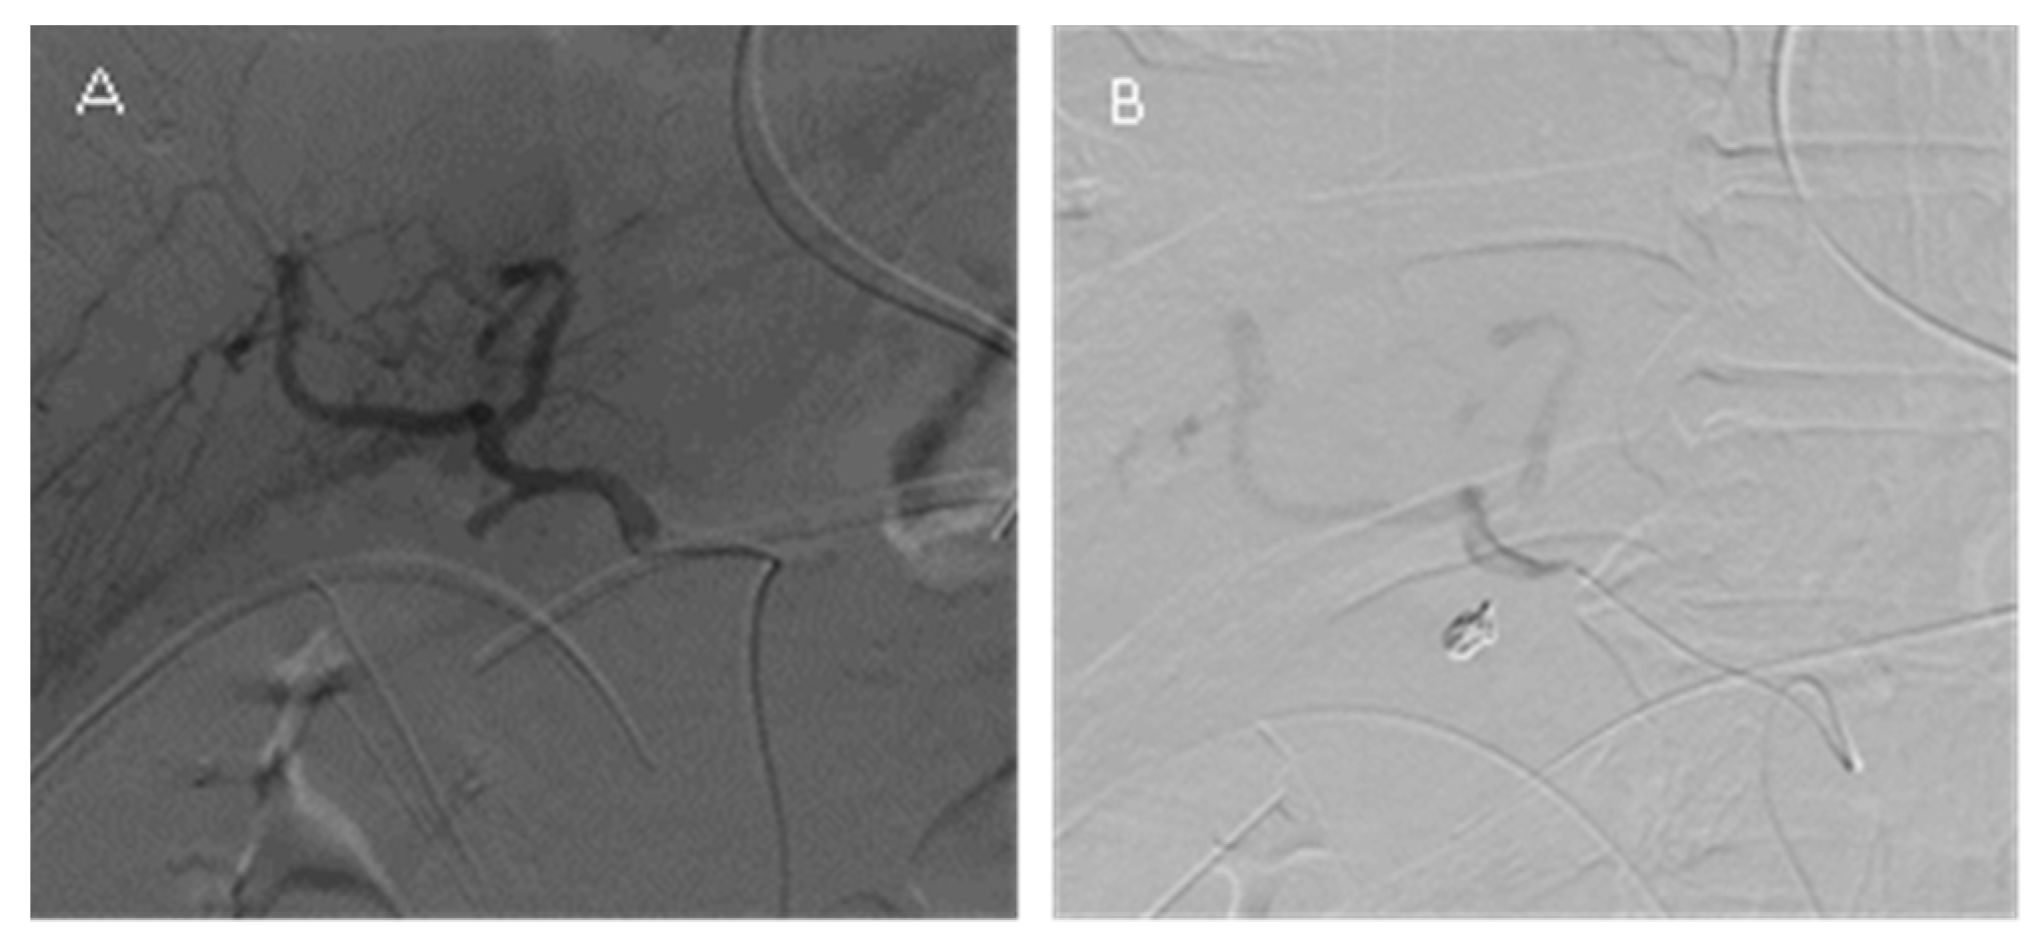

Procedures in the Ystentassisted coil embolization. (A) Wove a

Procedures in the Ystentassisted coil embolization. (A) Wove a Coil Embolization Semi-Jailing we describe a modified jailing technique that improves catheter maneuverability and report the safety and efficacy of the. intracranial stents that assist coil embolization are commonly deployed to avoid coil protrusion into the parent artery. Coil Embolization Semi-Jailing.